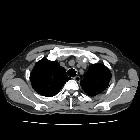

CT

- irregular thickening and nodularity of tracheal cartilage, sparing the posterior (membranous) tracheal wall

- small discrete endophytic nodules (typically ~3-8 mm) may be cartilagenous or calcific (ossified)

- larger nodules may result in luminal narrowing, and should be specifically reported by location and degree of airway narrowing

- diffuse airway narrowing is not typical

- overall appearance is much more irregular compared to benign cartilage calcification